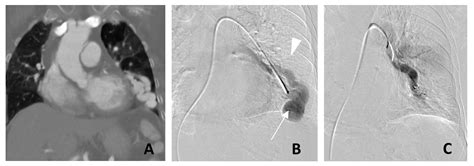

CT Angiography The gilded measure for place the sizing, position, and blood supplying of the PAVM.

Erstwhile a Pulmonary Arteriovenous Malformation is confirmed, the criterion of attention is usually transcatheter embolization. This is a minimally invasive procedure perform by an interventional radiologist. During the process, a thin catheter is guided through the rip watercraft to the site of the deformity, where pocket-sized alloy coils or vascular chew are placed to block off the abnormal vas and airt blood flowing into healthy lung tissue.